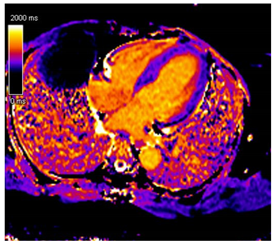

Amyloid deposition affects myocardial tissue architecture, which results in elevated intrinsic, non-contrasted myocardial T1 signal (native T1 mapping) []. The progression of amyloid CM can be quantitively monitored with native T1 elevation, which correlates with the degree of amyloid infiltration []. Amyloid fibril deposition can also cause myocardial edema. The increased water content in tissue prolongs T2 time, which is the relaxation time of protons in the transverse plane. However, T2 time in amyloid CM is usually shorter than that reported in myocarditis or myocardial infarction [].

Post-contrast CMR imaging provides information about the extracellular space, which in amyloid CM is distorted by amyloid deposition. In amyloid CM, TI-scout images for gadolinium kinetics show a simultaneous nulling of the blood pool and myocardium or a reverse null pattern where the myocardium nulls prior to the blood pool []. LGE patterns in amyloid CM range from absence to subendocardial or transmural, correlating with the severity of infiltration. LGE often involves all cardiac chambers. Contrast-enhanced T1-weighted imaging can be used to estimate extracellular volume (ECV), which is often markedly increased in amyloid CM (>40%) due to extracellular amyloid deposition []. Elevated ECV was shown to precede LGE in certain cases with a high probability of amyloid CM, likely signaling early disease []. However, the use of Gd to evaluate LGE and ECV may be precluded in patients with advanced kidney disease. Other contrast-free analyses of CMR that can help distinguish amyloid CM include longitudinal strain analysis. Similar to echocardiography, CMR shows globally reduced longitudinal strain in amyloid CM with relative apical sparing with specificity to distinguish CA of 82% but sensitivity of only 43% []. If Gd can be administered, the LGE ratio between base and apex, in addition to the relative strain ratio, was shown to have a higher discriminatory ability to distinguish amyloid CM from other causes of LVH []. Key CMR findings in amyloid CM are summarized in Table 1.